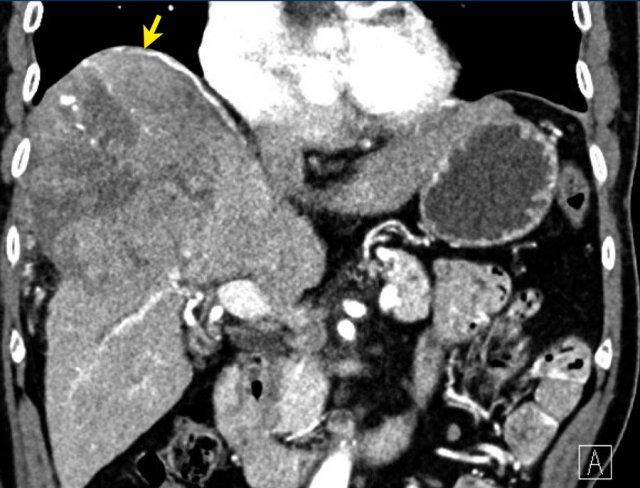

Hình ảnh mặt phẳng coronal cho thấy một tổn thương lớn đã được điều trị bằng TACE với các vùng ngấm thuốc thì động mạch nhẹ và thải thuốc còn sót lại do nguồn cấp máu chưa được điều trị qua động mạch hoành (mũi tên vàng): LRTR còn khả năng sống.

Tiếp tục xem hình ảnh mặt phẳng axial …

Lưu ý có hình ảnh bờ không đều của mỡ phúc mạc phía trước do vỡ bao gan (mũi tên).

LRTR còn khả năng sống

Tiền sử cắt gan phân thùy II với khối u còn khả năng sống tại bờ cắt.

Lưu ý vùng ngấm thuốc thì động mạch và thải thuốc tiếp giáp với các clip phẫu thuật (mũi tên).

Đây là trường hợp LRTR còn khả năng sống.